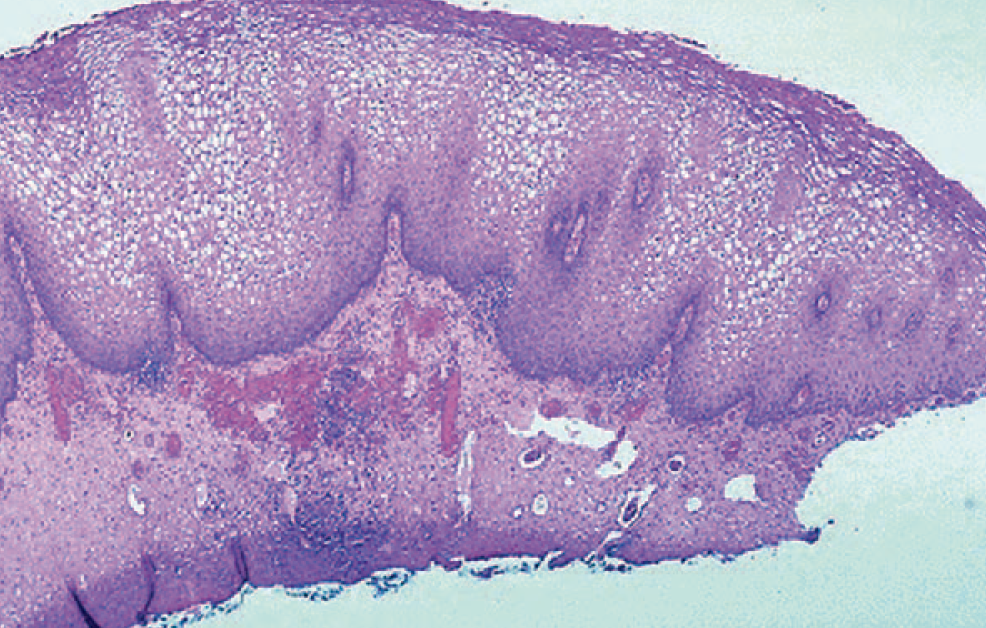

HPV showing cervical squamous metaplasia with vacuolized cells (koilocytic change)